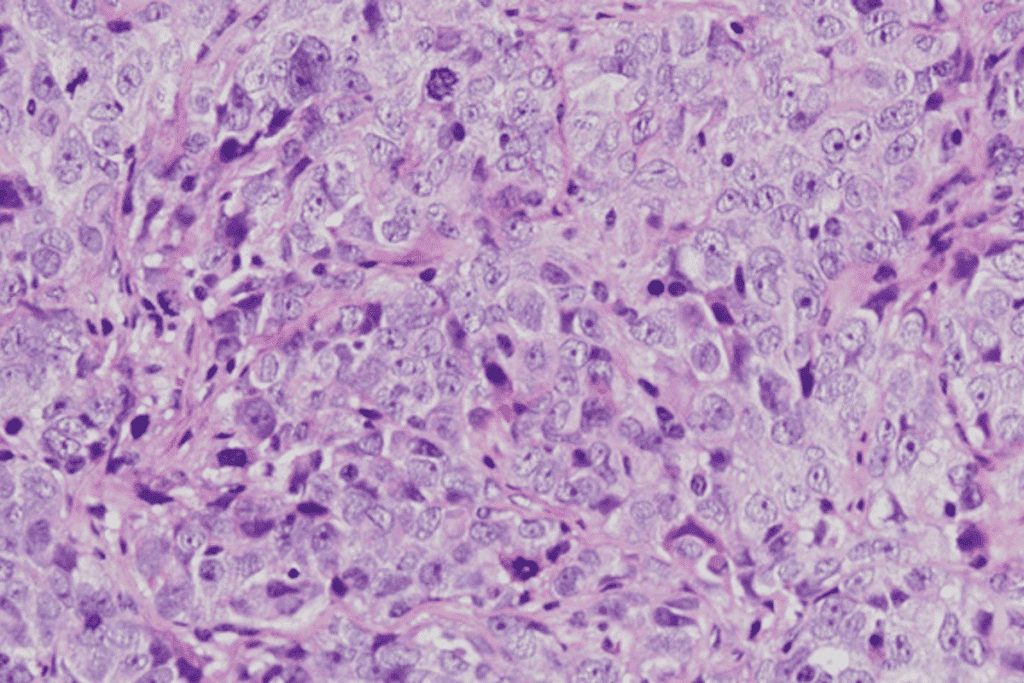

- Masses or Tumors: MRI scans can spot tumors in the brain, spine, and organs.

Potentially Serious Brain Abnormalities

Some MRI results show serious issues that need quick action. These include signs of stroke, tumors, or multiple sclerosis. Doctors and radiologists must carefully look at these to decide what to do next.

For example, if an MRI shows a stroke, acting fast can help a lot. Finding a tumor might mean talking about treatments like surgery or chemotherapy.